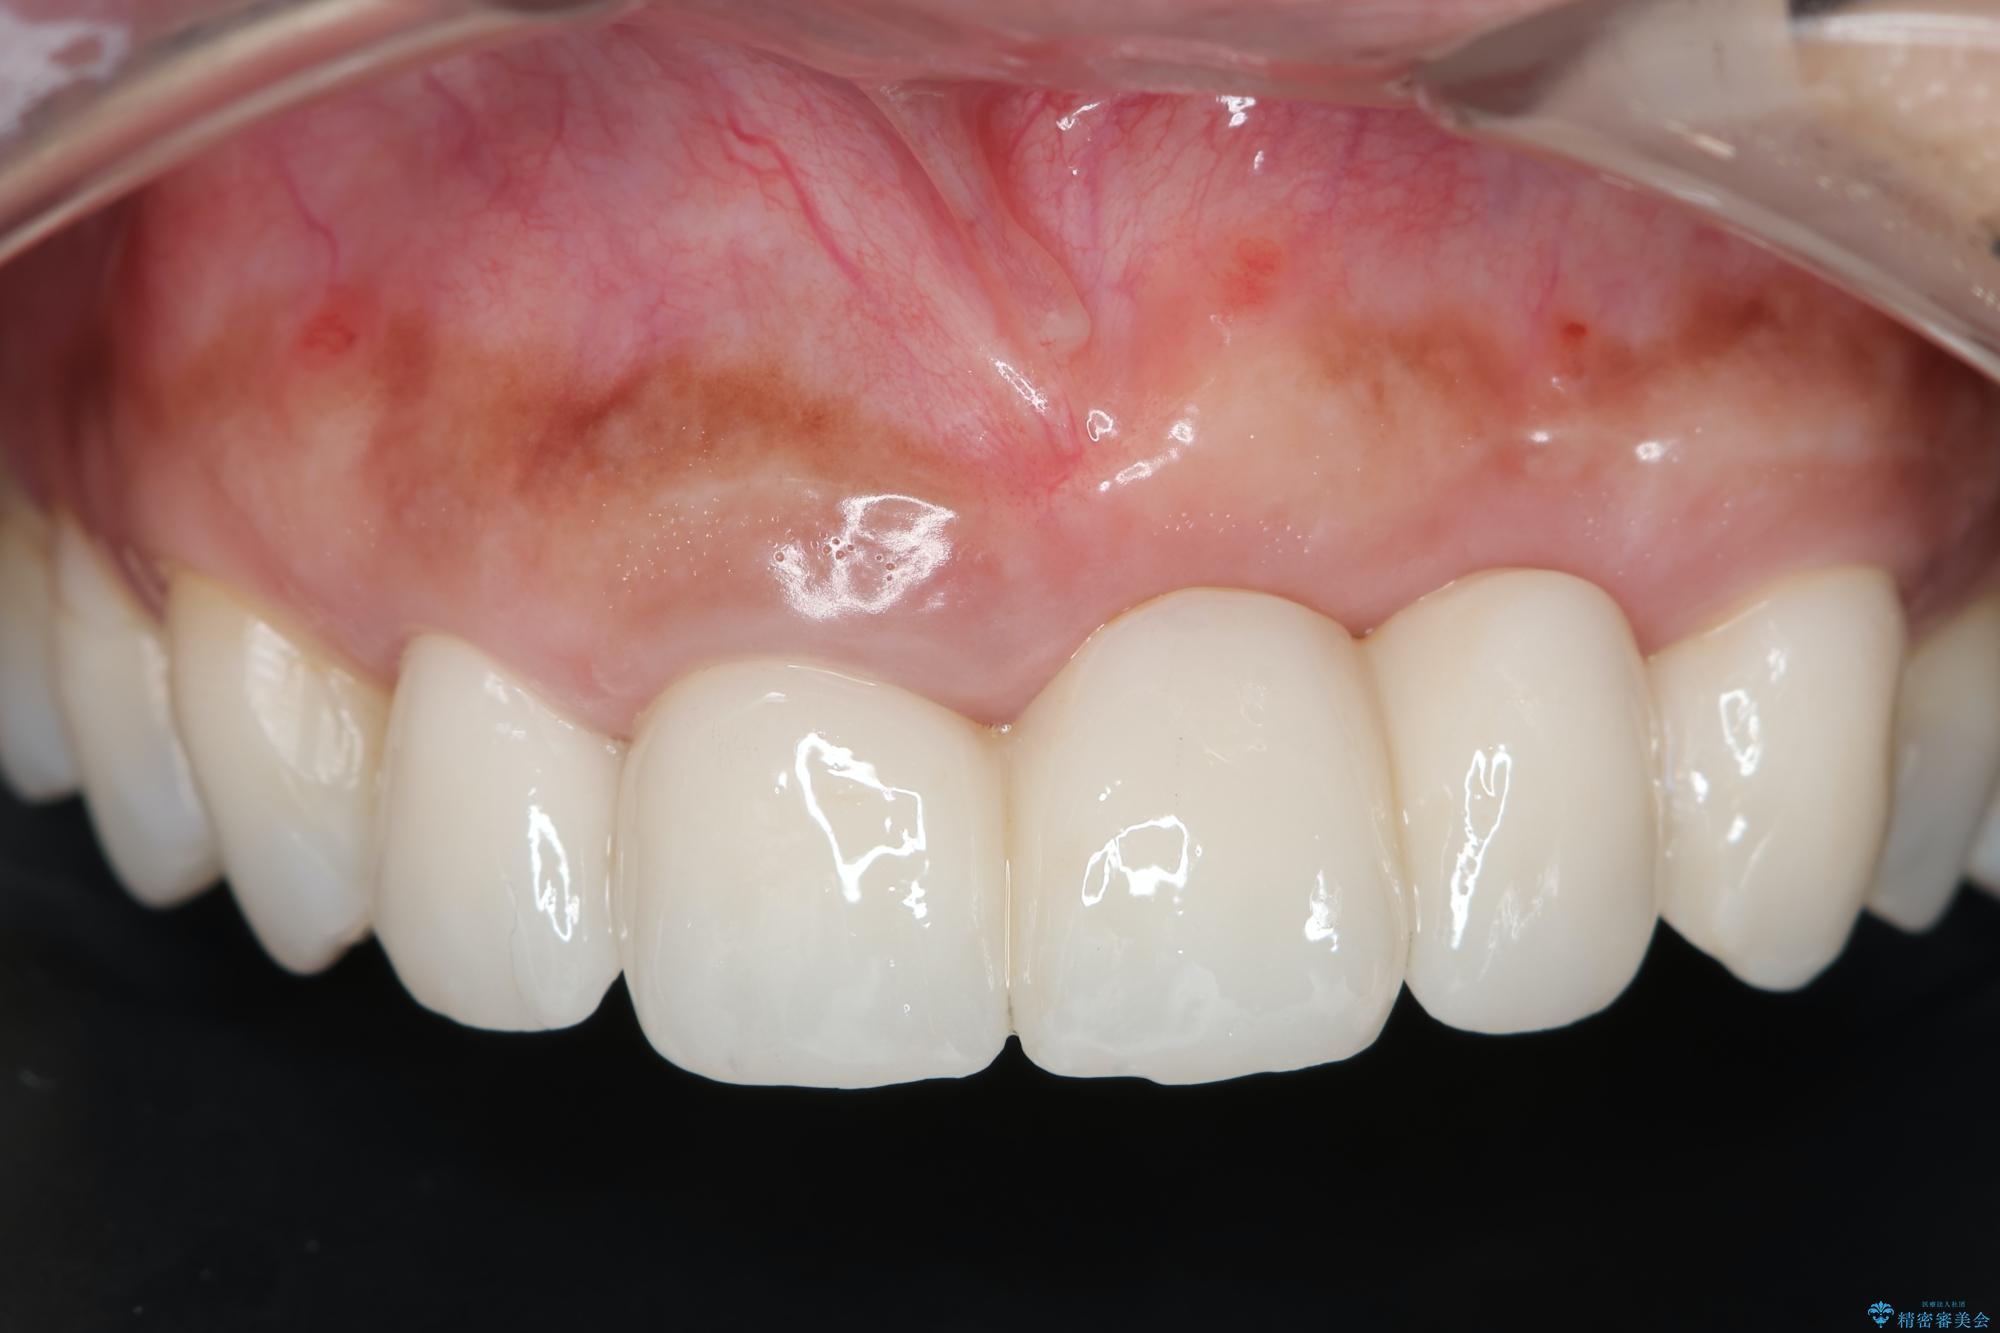

治療後

歯槽堤保存術を併用したブリッジ治療 治療後画像 歯槽堤保存術を併用したブリッジ治療 治療後画像 歯槽堤保存術を併用したブリッジ治療 治療後画像 歯槽堤保存術を併用したブリッジ治療 治療後画像 歯槽堤保存術を併用したブリッジ治療 治療後画像 歯槽堤保存術を併用したブリッジ治療 治療後画像 歯槽堤保存術を併用したブリッジ治療 治療後画像